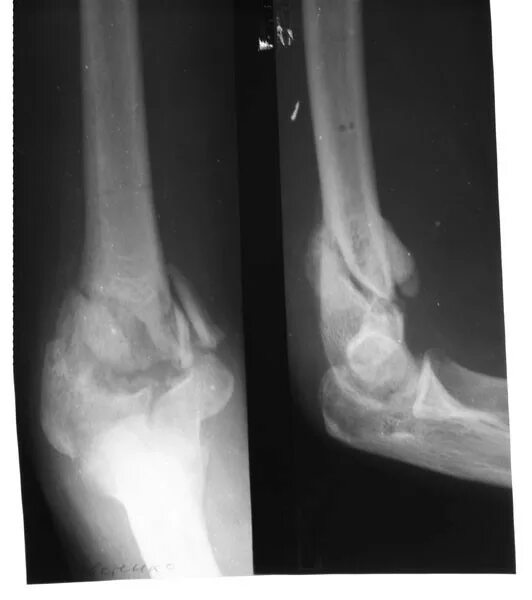

Оскольчатый перелом без смещения